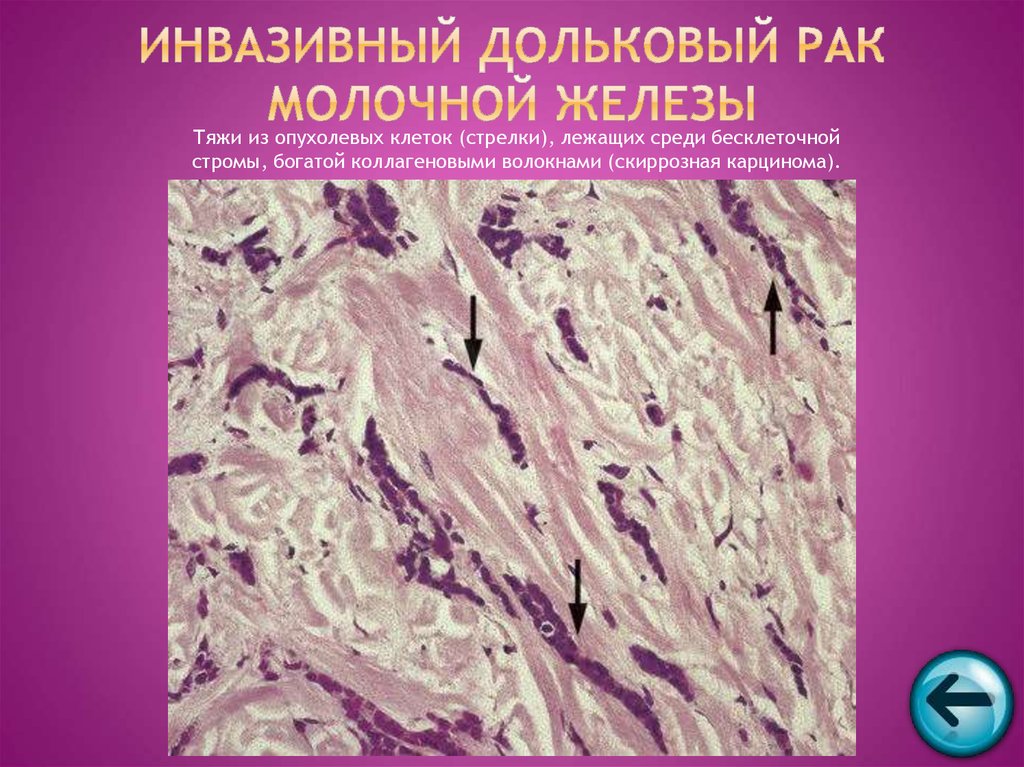

Исследование: микропрепарат молочной железы в медицине

Раздел: Снимки-откровения